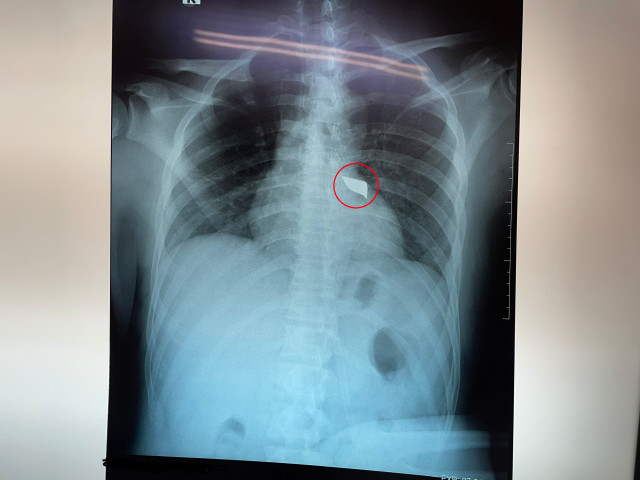

![]() |

| Dị vật nằm trong người bệnh nhân |

Tình trạng lúc nhập viện của bệnh nhân: bệnh tỉnh, niêm hồng, than đau lưng, khó thở nhẹ ,vết thương lưng thành ngực sau cạnh trái cột sống đoạn ngực 4-5 rỉ máu, còn dị vật, không tê yếu chi. Dấu hiệu sinh tồn ổn định.

Các bác sĩ nhanh chóng cấp cứu và thực hiện các xét nghiệm, siêu âm, chụp X-quang tim phổi thẳng, chụp cắt lớp vi tính lồng ngực …và tiến hành hội chẩn phẫu thuật và thống nhất phương án xử lý thám sát vết thương và lấy dị vật cấp cứu.

Sau 90 phút tích cực thực hiện, ca phẫu thuật thành công, lấy được mũi dao dài 5cm, rộng 2cm từ cột sống bệnh nhân ra. Hiện tại tình trạng bệnh nhân tỉnh, dấu hiệu sinh tồn ổn định